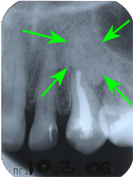

Es erstaunt nicht, dass die häufigsten Misserfolge von Wurzelbehandlungen sogenannte insuffiziente Wurzelfüllungen sind, also solche, die nur einen Teil der Wurzelkanäle abfüllen. Im restlichen, nicht abgefüllten Wurzelkanal verbleibt das abgestorbene Zahnmark, das als totes, eigenes Gewebe immer einerseits eine Entzündung auslöst und anderseits wird dieses marktote Gewebe von Fäulnisbakterien besiedelt, die eine Infektion im Knochen verursachen. Im Röntgenbild bezeichnet man einen solchen Herd als Zahngranulom (dunkle Flecken an der Wurzelspitze des Zahnes).

Die Infektion eines solchen Zahngranuloms im Knochen kann chronisch verlaufen, tut kaum weh, kann aber andere Organe im Körper über die Blutbahnen anstecken (infizieren) oder akut verlaufen, was mit irrsinnigem Zahnweh bis zum Abszess verbunden ist. Somit ist verständlich, dass tote, sogenannt devitale Zähne bei einem allgemein zahnärztlichen Untersuch geröntgt werden müssen, auch wenn sie nicht weh tun. Anhand zweier Fallbeispiele wollen wir das Thema Endodontie erläutern:

Ein 32 Jahre alter Mann kommt im November 1984 mit Zahnweh am unteren linken, zweithintersten Molaren (Backenzahn) in die Praxis. Das Röntgenbild von Abb. 1 zeigt insuffiziente Wurzelfüllungen bei allen drei Wurzelkanälen und an den Wurzelspitzen sogenannte Granulome, sichtbar als schwarze Flecken (grüne Pfeile in Abb. 1).